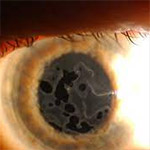

Fuchs' Corneal Dystrophy

An inherited condition that affects the inner layer of the cornea.